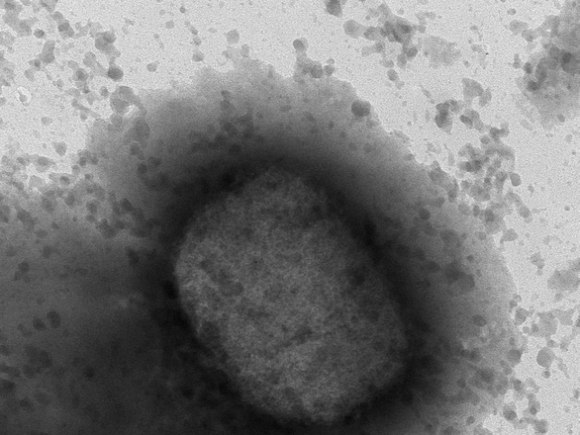

Virus gây bệnh đậu mùa khỉ trên kính hiển vi điện tử - Ảnh: AP